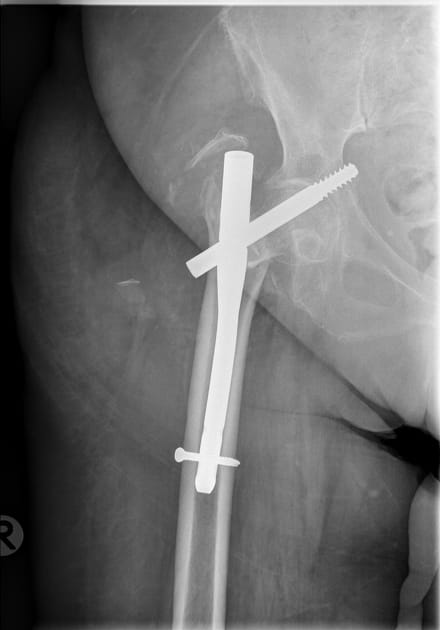

Most hip fractures require surgery. Surgeons either repair the break with a screw through the core of the femur or replace the joint with a full or partial replacement. The typical recovery timeline stretches three to six months, though some people need up to a year to reach their maximum improvement. Here are the stages to recovery: